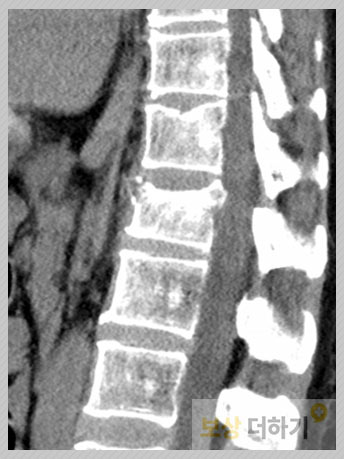

사례 1. 허리 골절

서울에 거주하시는 김 ** 님은 음식점에 들어가시다가 출입문에 부딪히셨고, 넘어지면서 엉덩방아를 찧어 허리 골절이 되는 사고를 당하셨습니다. · L1 압박골절 · 보존 치료 (보조기)

장해 진단서 발급 거부 김 ** 님의 주치의 분은 유합술이나 시멘트술을 한 것이 아니라 후유장해 진단서 발급에 특히 부정적인 반응을 보였습니다. 이때 적절히 대응하지 못한다면 진단금 청구 자체를 할 수가 없습니다. 안타깝게도 이러한 상황은 생각보다 자주 발생합니다. 손해사정사의 역할 다친 것도 서럽고 불편한데 마땅히 받아야 할 보상을 놓치는 일이 있어선 안 되겠죠! 따라서 후유장해 진단금 청구는 손해사정사의 도움을 받는 것이 좋습니다. 손해사정사는 가입자가 이해하기 어려운 약관, 보상 항목에 대해 명확히 알고 적용하며 장애 평가에 있어 어려움이 생기거나 누락, 오차에 대비하여 필요한 준비를 합니다. 2천만 원 지급 그럼, 저희 업체에서 도움을 드린 김 ** 님의 보상 결과는 어땠을까요? 장해 평가 및 보험사와의 분쟁 등 여러 가지 쉽지 않은 상황 가운데서 전반적으로 진행을 도와드린 결과 2천만 원 이상을 지급받으셨습니다.